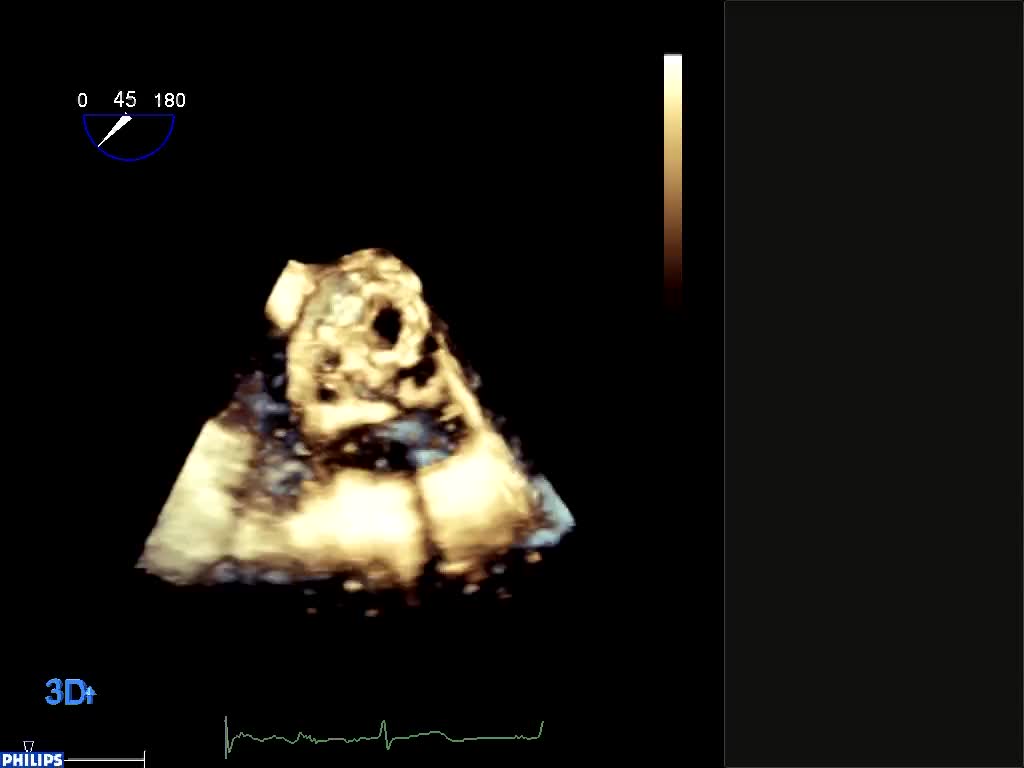

Protesi biologica mitralica Carpentier 25Autore: Daniela Torta

Categoria: Videoalbum

Parole chiave: biologica diagnosi ecotee3d protesi -